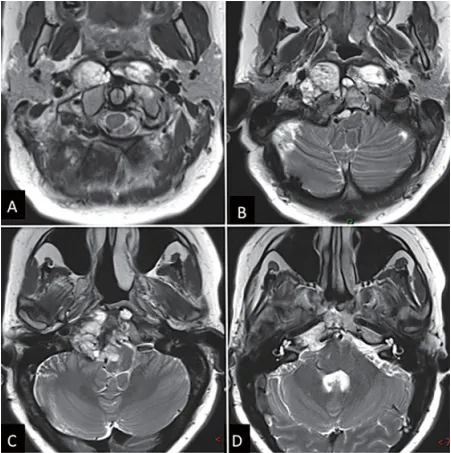

这很有可能是一个斜坡嵴索瘤,现在有332633mm这么大,已经侵袭左侧海绵窦,导致垂体移位、垂体柄歪斜,但手术风险很大,家属要慎重考虑。 几月前,小海的父母被医生告知了这一噩耗。尽管...

脊索瘤是罕见的骨恶性肿瘤,复发风险高,复发患者的长期生存情况难以预料。脊索瘤是起源于头尾轴沿线、从斜坡到骶骨的脊索残余组织。尤其颅底脊索瘤的诊疗具有特殊挑战性,需要多学科...